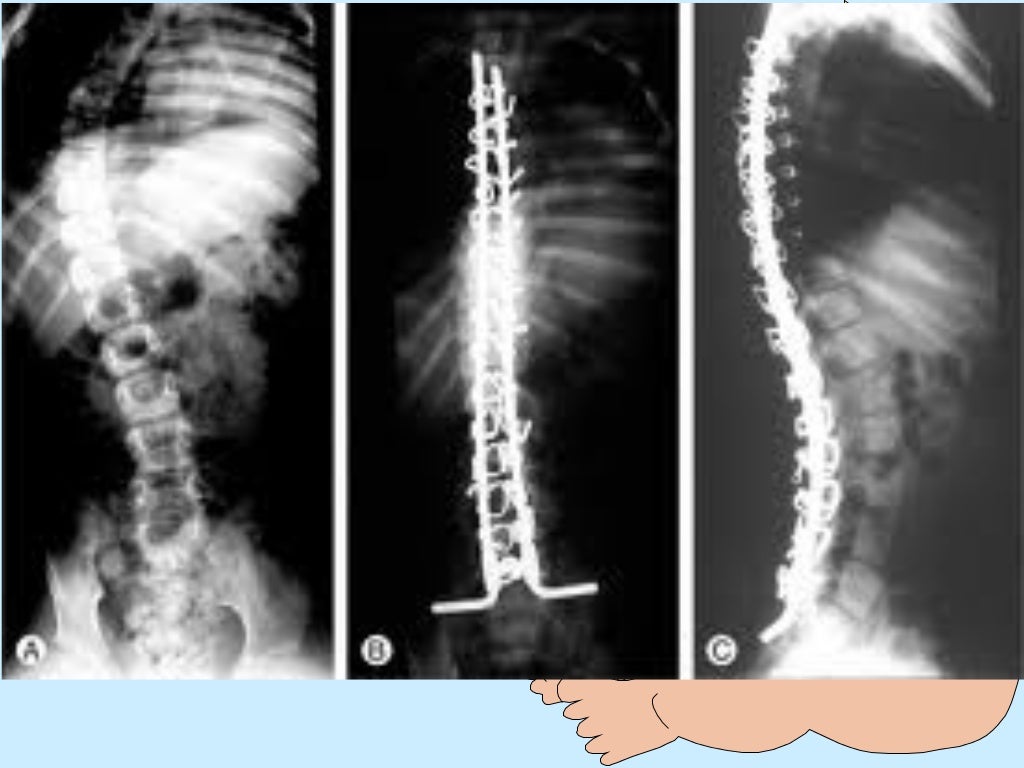

امراض العضلات عند الاطفال- Pediatric Muscle dystrophy- تكبير العرض